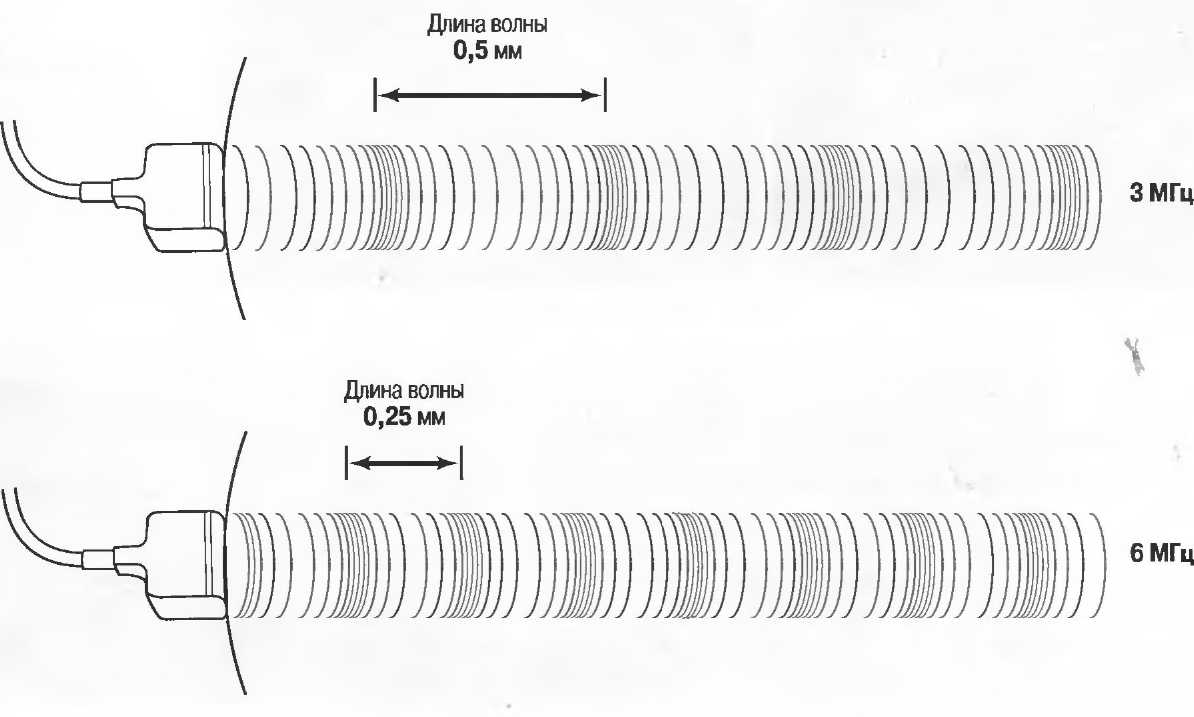

Длина волны

Длина ультразвуковой волны обратно пропорциональна частоте излучения. Чем выше частота излучения, тем короче длина волны. Например, ультразвук с частотой 3 МГц имеет длину волны 0,5 мм в мягких тканях, в то время как ультразвук с частотой 6 МГц имеет длину волны 0,25 мм. Чем короче волна, тем выше разрешающая способность, позволяющая получать более четкое и более детальное изображение на экране. Однако длина волны также влияет на глубину проникновения ультразвука (см. «Затухание»).

Затухание

Ткани тела поглощают и рассеивают ультразвук по-разному. Высокие частоты поглощаются и рассеиваются (гасятся) в большей степени, чем низкие. Поэтому, чтобы достичь более глубоких тканей, необходимо использовать более низкие частоты, так как менее вероятно, что эти волны затеряются при прохонодении через ткани. На практике оптимально использовать частоту около 3,5 МГц для глубокого сканирования у взрослых и частоту 5 МГц и выше для исследования более худых пациентов или детей. Частота 5 МГц и выше используется для исследования поверхностных органов у взрослых.

Высокие частоты дают более детальное изображение, но имеют меньшую проникающую способность.

Частота и разрешающая способность

Чем выше частота ультразвукового излучения, тем выше разрешающая способность. Это означает, что при использовании более высокой частоты возможна визуализация более мелких структур. Одновременно проникающая способность ультразвуковой волны в ткани становится меньше. Сканирование, таким образом, является компромиссом; при этом используется максимально высокая частота, достаточная для проникновения на заданную глубину (рис. 11).